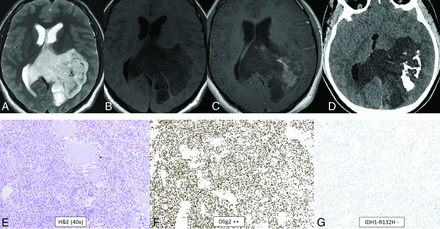

Polymorphous low-grade neuroepithelial tumor of the young. It is a cortical/subcortical mass on T2-FLAIR (A) and T2-weighted images (B) with a cystic (“bubbly”) appearance, some suppression of fluid signal on the FLAIR image, and faint heterogeneous enhancement (C) within the right inferior parietal lobule (arrows). CT shows faint specks of calcification within the lesion (D). Histology demonstrates a relatively well-demarcated low-grade neuroepithelial tumor with prominent dystrophic calcification (E). Tumor cells have oligodendroglial-like morphology and are strongly positive for CD34 (F), with low proliferative activity. Immunohistochemical stain is negative for IDH1 R132H (G) and positive for OLIG2. Chromosomal microarray identified loss of 10q21.3q26.13 disrupting CTNNA3 and FGFR2, representing a FGFR2-CTNNA3 fusion.

Diffuse Low-Grade Glioma, MAPK Pathway–Altered